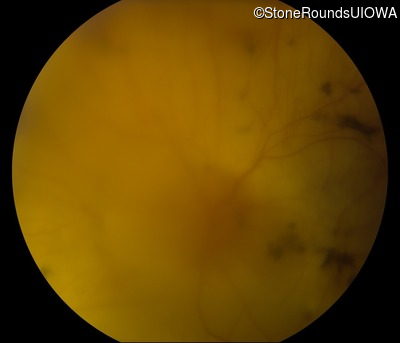

Fundus Photography - Right - Hand Motion 6"

Exemplar